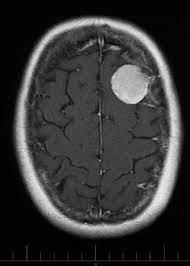

Extracted image Detected image

Fig.6 Demonstrationofresultwithfivedetectedtumours